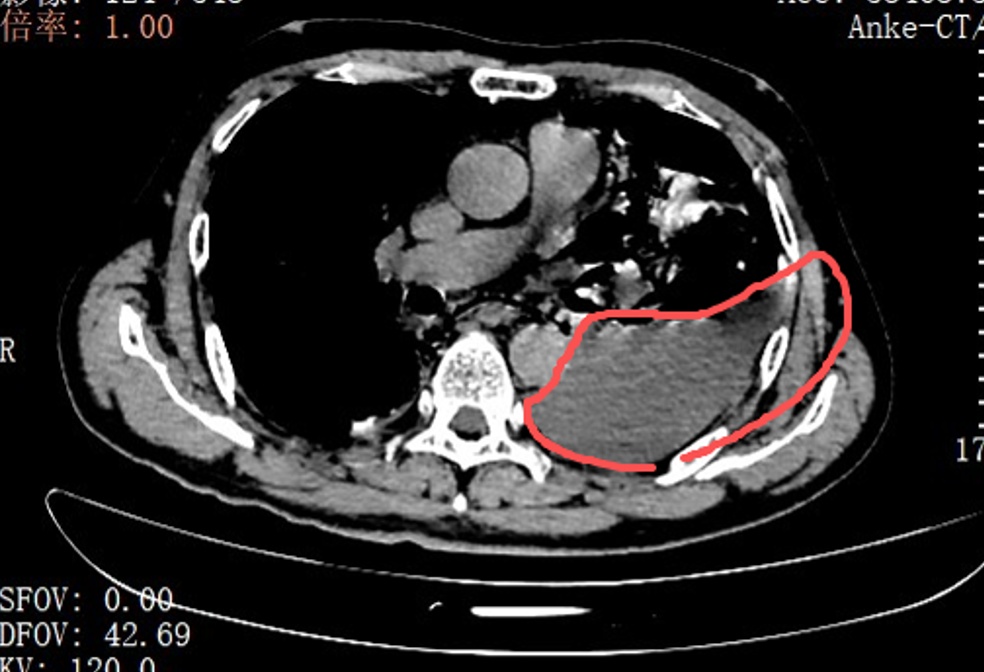

确诊后,胸外科手术团队当天即为张叔实施了胸腔镜下食道修补微创手术。打开胸腔后,眼前的一幕让医护人员震惊:整个左侧胸腔内充斥着叉烧包的菜叶、食物残渣,与脓液、消化液混合在一起。

手术团队花费了很长时间,才用吸引器一点点将这些污染物清理、冲洗干净。随后,他们找到了食道下段那道10厘米长的裂口,并用可吸收线小心翼翼地进行分层修补。

红圈区域是食物残渣、消化液破入食管